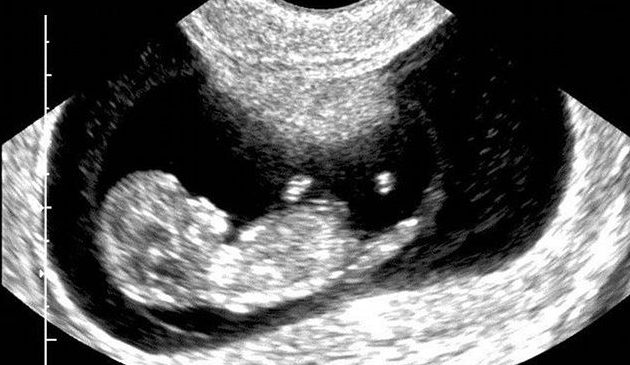

La Vita stava nascendo dentro di me. Quel cuoricino così piccolo stava già facendo miracoli. Cari amici, quest’oggi riportiamo la testimonianza di Lucia che ci ha raccontato di una tenacia nel proteggere il proprio figlio, anche di fronte a innumerevoli difficoltà. Ora ha una bellissima […] uniperlavita2 9 febbraio 2021 1 commento